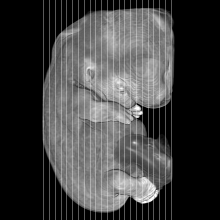

MRI Slice Selector

Mouse: click on a line below to select a view

Finger: tap a line below with a very light touch